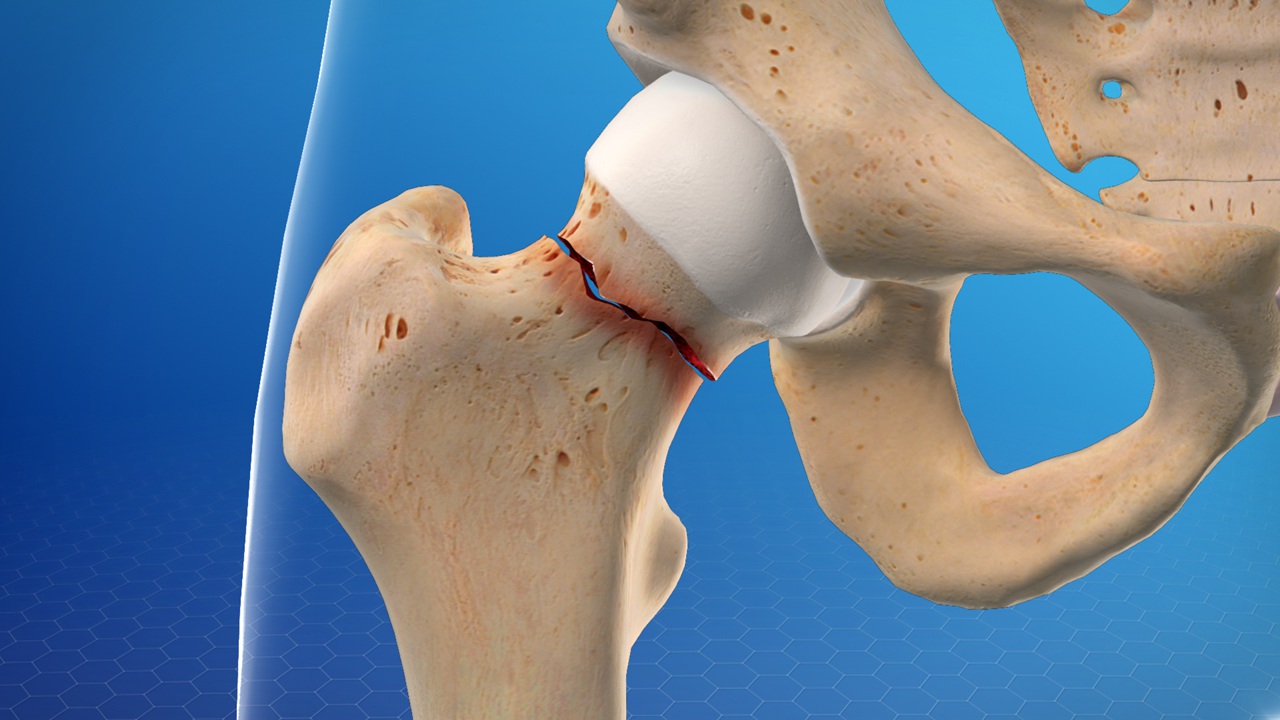

یک متخصص ارتوپدی اغلب میتواند شکستگی لگن را بر اساس علائم و موقعیت غیرمعمول لگن و پا تشخیص دهد. عکسبرداری با اشعه ایکس معمولاً شکستگی را تأیید میکند و محل شکستگی را نشان میدهد. به دنبال جراحی و درمان شما را به کاردرمانی در نارمک ارجاع می دهد و روند توانبخشی خود را با متخصصین کاردرمانی در نارمک پیگیری خواهد کرد

در روند اولیه درمان، اگر عکسبرداری با اشعه ایکس شکستگی را نشان ندهد اما همچنان درد لگن داشته باشید، متخصص ارتوپدی یا جراح استخوان و مفاصل ممکن است آزمایشهای تصویربرداری بیشتری را تجویز کند. امآرآی یا اسکن استخوان میتواند شکستگی مویی را تشخیص دهد.

بیشتر شکستگیهای لگن در یکی از دو محل روی استخوان بلندی که از لگن تا زانوی شما امتداد دارد و فمور نامیده میشود، رخ میدهد:

گردن استخوان ران

این ناحیه در قسمت بالایی استخوان ران شما، درست زیر قسمت گوی شکل، به نام سر استخوان ران، از مفصل گوی و کاسهای قرار دارد.

ناحیه اینترتروکانتریک

این ناحیه کمی پایینتر از مفصل ران، در قسمتی از استخوان ران بالایی که به سمت بیرون بیرون زده است، قرار دارد.